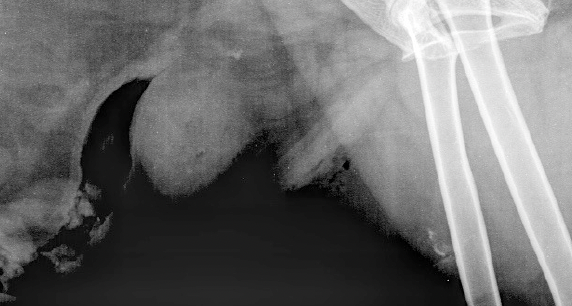

Q

Cas 1: Ti-mine, un chat mâle castré de 10 mois est présenté pour une boiterie importante au MPG d’apparition aiguë

A. Je ne vois rien, donc ce doit être psychosomatique

B. Trauma au niveau des tissus mous

C. Avulsion de la tubérosité tibiale

D. J’hésite et je voudrais essayer une projection additionnelle

A